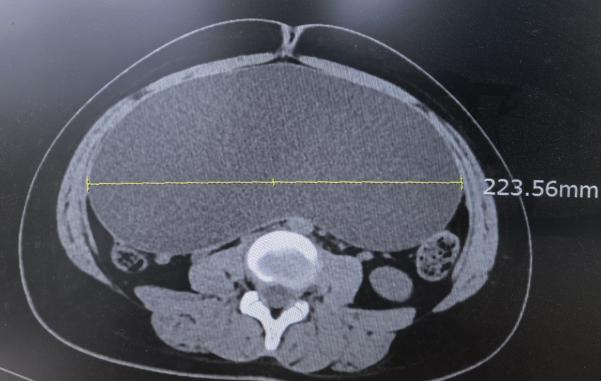

该患者是一名21岁的少女,正值花季,却因腹部明显膨隆而陷入深深的烦恼中,影像学检查提示腹腔内存在一直径超过20厘米的巨大囊性肿瘤,上至剑突,下达盆腔,来源与性质不明,手术难度与风险较高。外院曾建议行传统开腹手术。

9月17日,普外科、妇产科、手术室、麻醉科共同联合为患者实施手术。术中,在麻醉与手术室的密切配合以及妇产科主任刘晓碧的会诊指导下,施雪松主任与王超主任凭借丰富经验与娴熟技巧,在腹腔镜高清视野下精细操作,完整剥离并移除了巨大囊肿,吸出囊液约4500毫升,手术过程顺利,出血量极少。几个“钥匙孔”大小的小孔,取代了传统近30厘米的长切口,完整切除病灶的同时,也守护了患者的健康与自信。